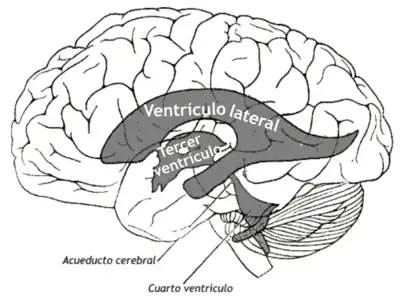

En el cerebro existen cuatro cavidades anatómicas denominadas ventrículos cerebrales, se encuentran interconectados entre sí, y constituyen el sistema ventricular por el que circula el líquido cefalorraquídeo.

Los ventrículos laterales están situados a lo largo de ambos hemisferios cerebrales y constan de un asta anterior que se dirige a lóbulo frontal, un asta posterior que se dirige a lóbulo occipital y un asta inferior que se dirige hacia abajo y hacia delante en el lóbulo temporal. Los ventrículos laterales están conectados al tercer ventrículo a través del orificio interventricular de Monro (entre la columna del fórnix y el extremo rostral y medial del tálamo). El tercer ventrículo es una delgada cavidad aplanada situada entre los tálamos y atravesada por la comisura intertalámica. Está conectado con el cuarto ventrículo a través del acueducto cerebral o Silviano. Finalmente, el cuarto ventrículo está situado entre el tronco cerebral y el cerebelo. Del cuarto ventrículo sale el líquido cefalorraquídeo (LCR) al espacio subaracnoideo a través de los agujeros de Luschka y el agujero de Magendie. Los ventrículos se continúan en la médula espinal a través del canal ependimario, una estrecha cavidad que nace al final del cuarto ventrículo y recorre internamente la médula espinal hasta el cono medular donde termina, es decir en el borde inferior de L1.

El LCR se crea en los plexos coroideos de los ventrículos laterales, tercero y cuarto, viajando desde el ventrículo lateral al tercero y al cuarto para continuar por el canal ependimario o descargar al espacio subaracnoideo a través de los orificios de Luschka y Magendie. Recorre todo el espacio subaracnoideo para finalmente ser absorbido en las granulaciones aracnoideas, localizadas en los senos venosos, principalmente en el seno sagital superior